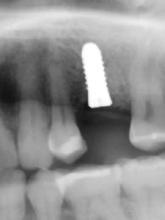

3. a–b ábra: Röntgenfelvételek három hónap után (a) és a gyógyulási csavarok behelyezve (b, 1. eset).

4. a–b ábra: Röntgenfelvételek öt hónappal később (a) és a gyógyulási csavarok behelyezve (b, 2. eset).

5. a–c ábra: Röntgenfelvételek öt hónappal később (a) és a gyógyulási csavarok behelyezve (b és c, 3. eset).

6. a–b ábra: Röntgenfelvételek öt hónappal később (a) és a gyógyulási csavarok behelyezve (b, 4. eset).